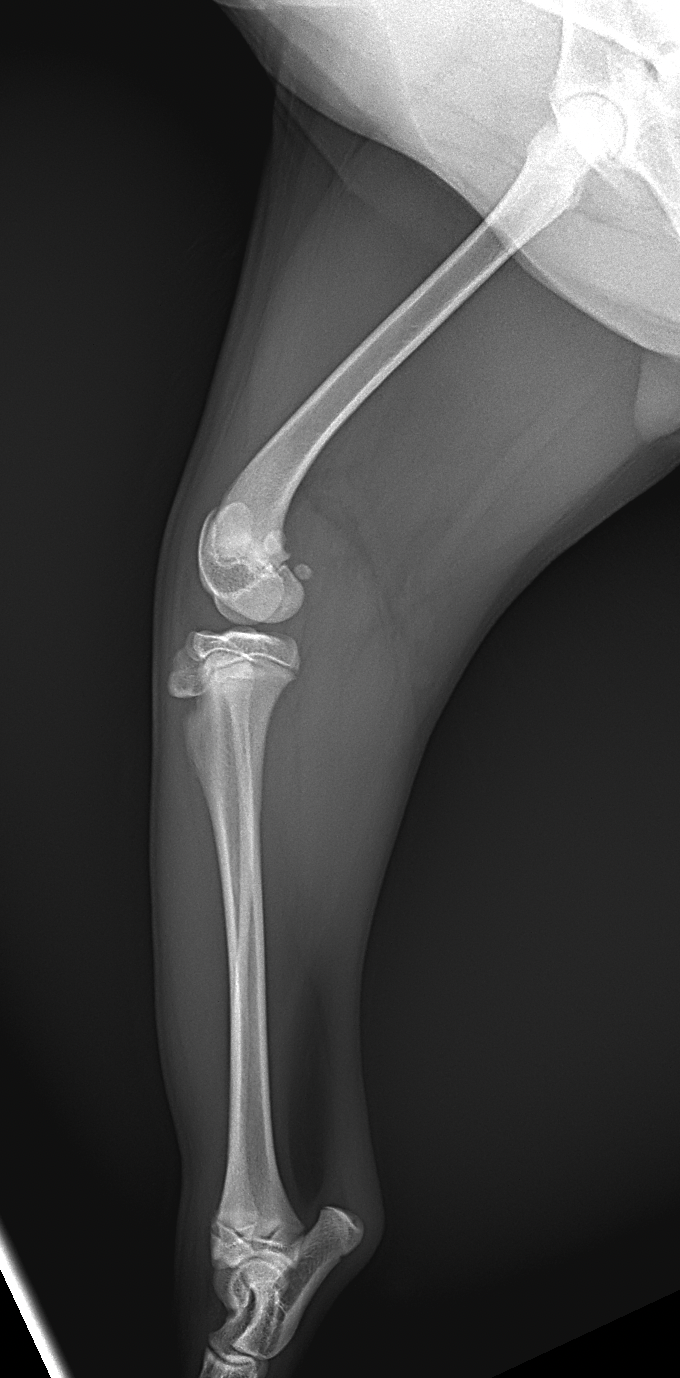

膝蓋骨内方脱臼G4により右後肢の負重が弱いという患者さんが紹介受診されました。膝蓋骨は大腿骨滑車から脱臼したままで大腿骨滑車内に誘導することができませんでした。大腿骨の変形などは幸い確認されませんでした。大腿骨滑車形成術、内側広筋の切離、脛骨粗面外側移行術、外側余剰関節包の切除によりアライメント手術を行いました。これから後療法も重要になります。